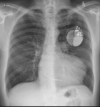

RN a termo.

Cardiomegalia massiva em um neonato com pulmão normal (sem edema alveolar ou intersticial, sem derrame pleural)

Cardiomiopatia neonatal.